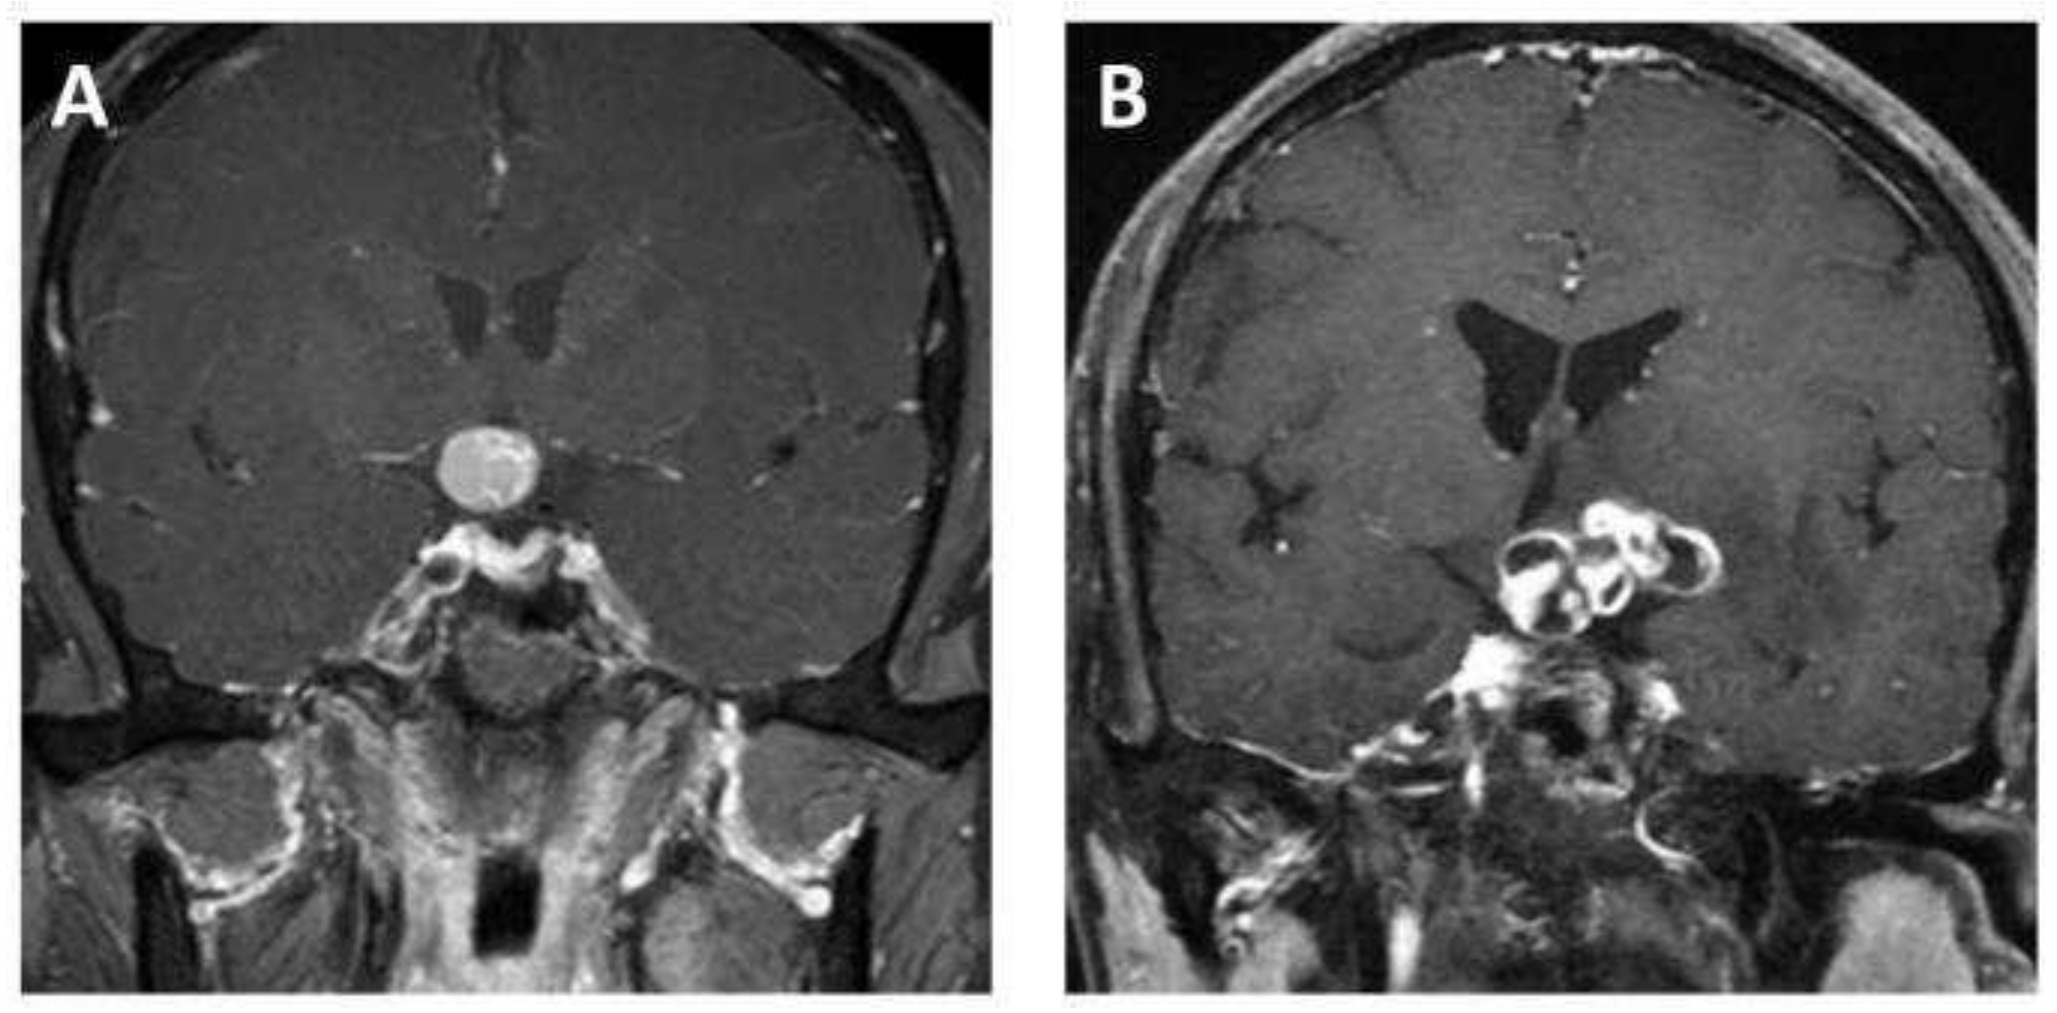

MR scans of the sellar region were performed on all eligible patients via a 3.0 T scanner (Signa Excite; GE healthcare, Milwaukee, WI, USA) in our institution. Coronal contrast-enhanced T1-weighted images were used in this study, as the tumor boundaries were much clearer on the enhanced images compared to the other sequences and coronal images are commonly used in clinical work, as they can provide more information about the relationship between a tumor and the surrounding structures. The parameters of the contrast-enhanced T1-weighted imaging were as follows: time repetition = 552 ms, time echo = 10 ms, field of view = 150 mm × 150 mm, data matrix = 256 × 256, and slice thickness = 5 mm. The contrast-enhanced images were acquired within 200 s after the injection of the contrast agent, gadopentetate dimeglumine (dose: 0.1 mmol/kg). The images were exported from the picture archiving and communication system (PACS). Figure 2 shows examples of ACP and PCP, respectively.

Figure 2.

Representative contrast-enhanced T1-weighted MR images of (A) adamantinomatous craniopharyngioma and (B) papillary craniopharyngioma.